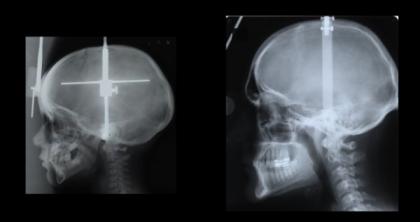

左为现代人类头骨,右为尼安德特人头骨。